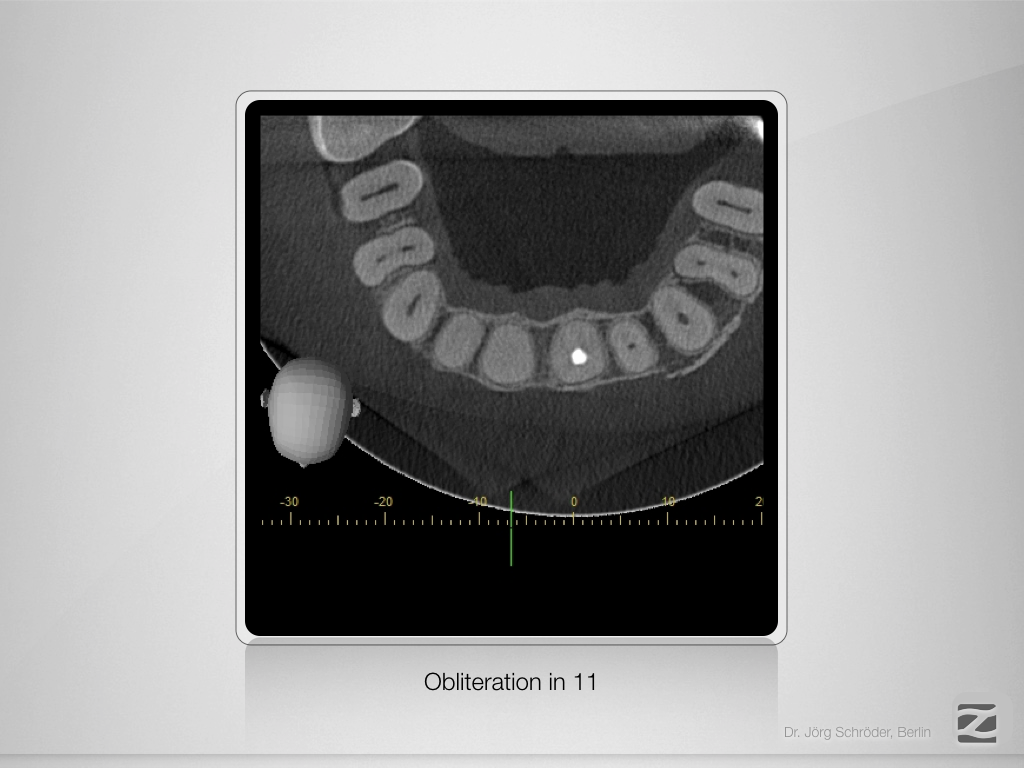

„Guided“ geplant und „Guarded“ gemacht